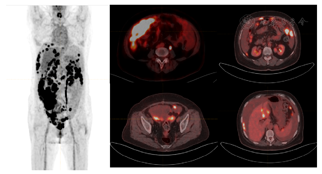

⑴胃镜(华山医院):胃窦炎(糜烂型,中度)。胃窦后壁活检病理:轻度慢性非萎缩性胃炎;肠镜:结直肠多发息肉,病理:乙状结肠增生性息肉,直肠管状腺瘤,降结肠管状腺瘤;⑵腹部增强CT(2022年7月27日):腹腔、腹膜多发种植转移灶并可疑累及右侧邻近腹壁,腹腔积液,盆腔多发种植转移灶,腹盆腔积液;⑶计算机体层血管成像(CT angiography,CTA)(2022年7月28日):右肺上动脉内少许栓塞;⑷正电子发射计算机断层显像/计算机断层显像(positron emission tomography/computed tomography,PET-CT)(华山医院2022年7月29日检查):大网膜、腹盆腔肠系膜、腹膜、肝脾包膜多发病灶(部分伴软组织影形成),伴FDG代谢不均匀异常增高,结合病史,考虑恶性肿瘤可能性大,建议右下腹腔大网膜病灶活检。双侧内乳及心膈角淋巴结FDG代谢轻度增高,考虑肿瘤浸润不能除外;腹盆腔大量积液。

⑴患者66岁,腹胀伴纳差2个月余;⑵体检发现腹盆腔大量腹水,移动性浊音阳性,右下腹巨大包块;⑶2022年7月26日肿瘤指标异常升高:CA199 67.2 U/ml,CA125 471 U/ml,CA724 27.5 U/ml,CA153 >300 U/ml,神经元特异性烯醇化酶19.2 ng/ml,偏高,CA50 61.96 IU/ml,HE4 804 pmol/L;⑷影像学检查:2022年7月29日华山医院PET-CT检查:大网膜、腹盆腔肠系膜、腹膜、肝脾包膜多发病灶(部分伴软组织影形成),伴FDG代谢不均匀异常增高(图1),结合病史,考虑恶性肿瘤可能性大,建议右下腹腔大网膜病灶活检。双侧内乳及心膈角淋巴结FDG代谢轻度增高,考虑肿瘤浸润不能除外。腹盆腔大量积液。